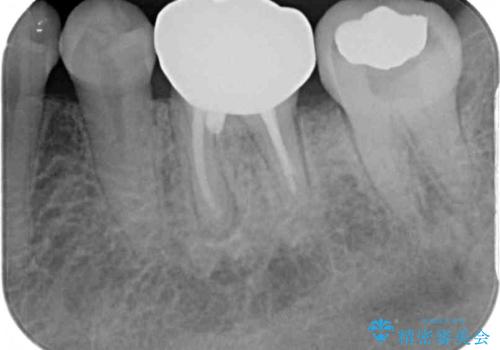

術後6ヶ月でレントゲン写真を撮影したところ、出血の原因であった穴付近の溶けていた骨が回復している様子が認められました。